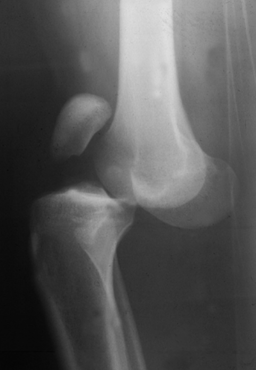

A 30 year old male presents with knee pain. His radiograph and biopsy are shown below. What is your diagnosis? Prognosis?

Benign giant cell tumor. These often occur in the epiphyseal regions of long bones and have a soap bubble appearance on x-ray. They also demonstrate spindle-shaped cells with multinucleate giant cells on a biopsy.